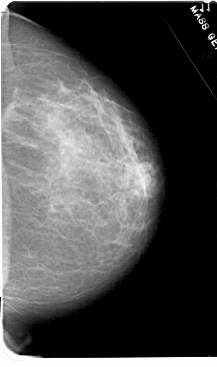

A_1607_1.RIGHT_CC

RIGHT_CC LINES 5491 PIXELS_PER_LINE 3241 BITS_PER_PIXEL 12 RESOLUTION 43.5 NON_OVERLAY